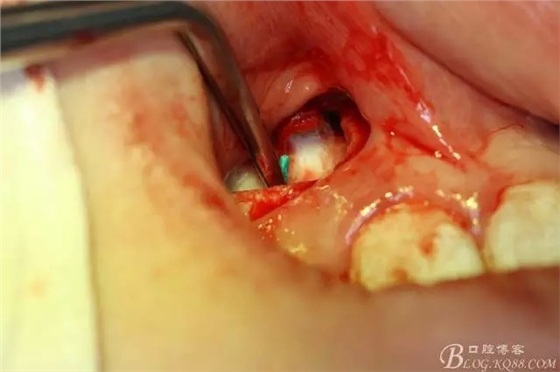

病例資料: 患者、柴xx、女、16歲。??茩z查及病歷如下圖: 患者同意我院正畸科建議,遂轉(zhuǎn)診倒外科。術(shù)前簽知情同意書。 治療過(guò)程: 圖1.術(shù)前的CBCT檢查:13阻生,疑為含牙囊腫??v剖面顯示12牙根吸收至根尖1/3。 圖2.局部麻醉下 。行唇側(cè)弧形切口,12松動(dòng)不到1°。 圖3.翻瓣、暴露骨面。 圖4.去骨、 暴露13牙冠 圖5.去骨、逐漸顯露13。 圖7.拔除13. 圖8.摘除囊壁 圖9.必須完整剝離囊壁。 圖10.摘除囊壁后形成的骨腔 圖11.超聲骨刀12根尖倒預(yù)備 圖13. 消毒棉球骨腔內(nèi)隔濕血液,紙尖干燥倒預(yù)備好的根管 圖14. 紙尖無(wú)血即可 圖15。MTA倒充填 圖16.骨腔填塞膠原蛋白海綿 圖17.拔除的13及摘除的囊壁 圖18.縫合 圖19.術(shù)后x線根尖片影像:MTA封閉根尖